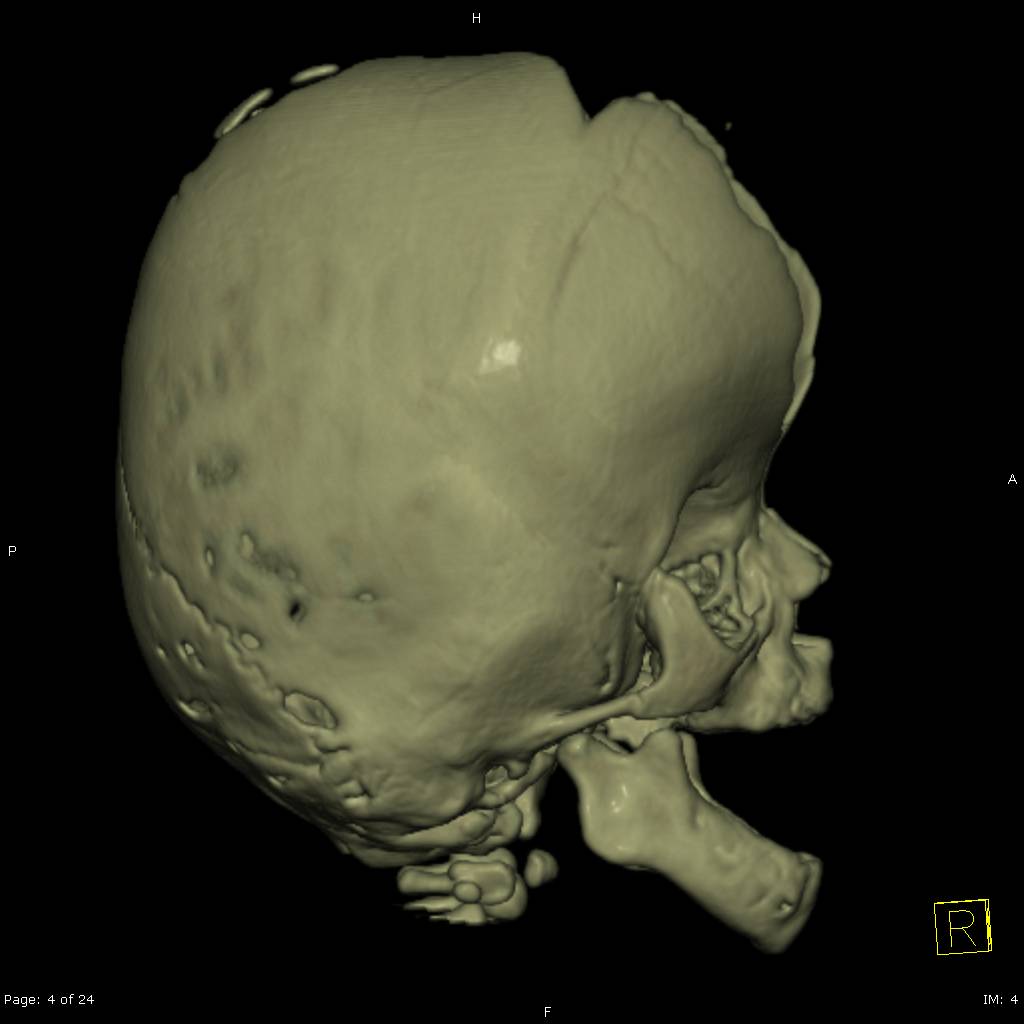

El Síndrome de Apert es un trastorno genético autosómico dominante causado por una mutación espontánea en el gen FGFR2, específicamente en el receptor 2 del factor de crecimiento de los fibroblastos. Esta anomalía genética provoca el cierre prematuro de las suturas entre los huesos del cráneo, una condición conocida como craneosinostosis, afectando la forma de la cabeza y la cara2.

- Craneosinostosis: Cierre prematuro de las suturas craneales, evidenciado por crestas a lo largo de las suturas.

El diagnóstico del Síndrome de Apert se basa en un examen físico detallado, radiografías y pruebas genéticas para identificar la mutación en el gen FGFR2. El tratamiento implica cirugía para corregir craneosinostosis y deformidades en manos y pies. Es crucial la intervención de equipos médicos multidisciplinarios especializados en cirugía craneofacial y genética.